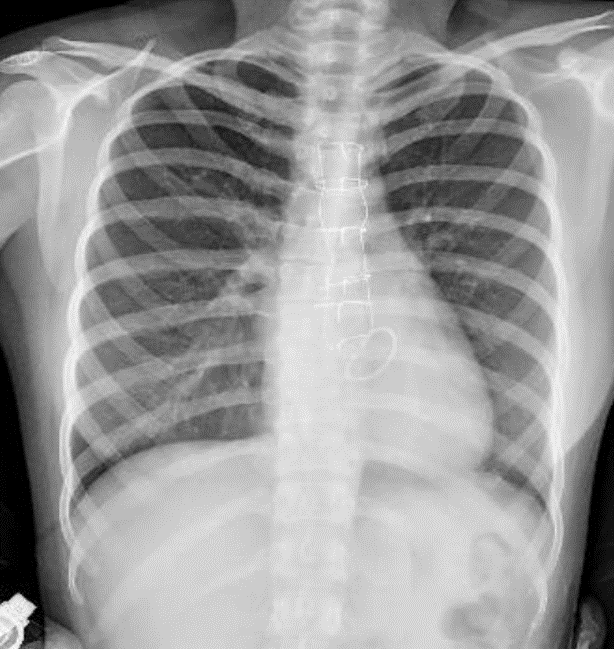

Hãy phân tích tình huống Nữ 31 tuổi CĐ: Phẫu thuật sữa val 2 lá, đặt vòng val 2 lá, hở val 2 lá vừa- nặng(thất trái lớn)

1-Chỉ kim loại thành ngực 2-Val 2 lá nhân tạo